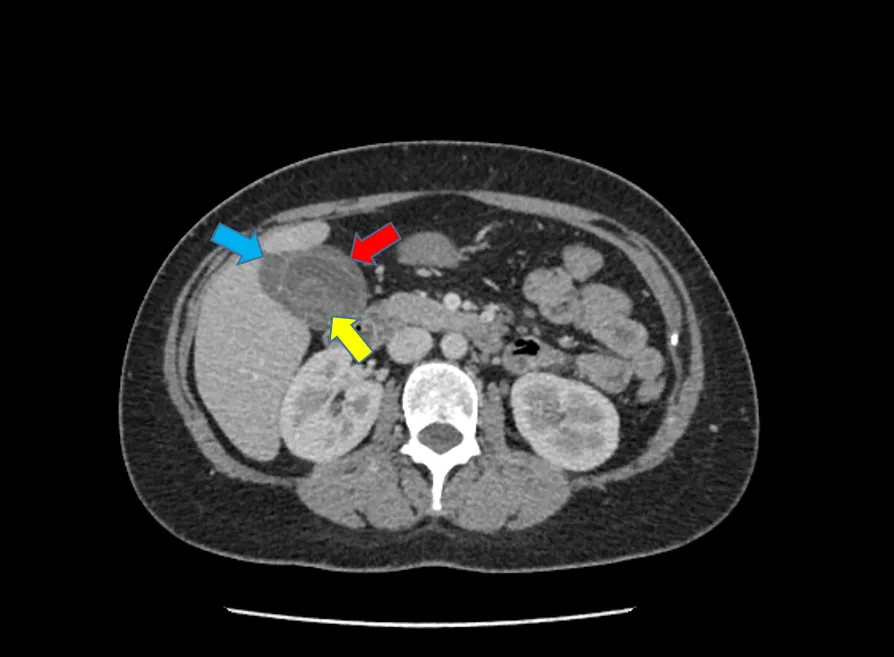

Figure 8: Cholelithiasis (gallbladder stones – yellow arrow) and cholecystitis (gallbladder inflammation manifested by thickened gallbladder wall – red arrow, and inflammatory fluid surrounding the gallbladder – blue arrow).

Acute cholecystitis is a condition that requires prompt medical attention and often necessitates hospital admission for intravenous antibiotics, anti-inflammatory drugs, fluids to correct dehydration, and symptomatic medications for nausea and vomiting. Blood tests are useful to assess the severity of liver function abnormalities, infective panel results, and blood cultures, which guide antibiotic selection. Patients should expect imaging procedures, such as an ultrasound and/or a CT scan, as a foundation to establish the diagnosis and evaluate the severity and complications of acute cholecystitis. These tests provide comprehensive clinical and diagnostic information to help doctors better understand your condition and discuss with you the potential need for surgery and its timing, when indicated.